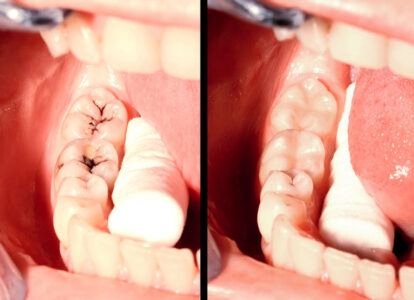

At Advanced Dental Care we believe in offering our patients what’s most appropriate from basically 3 alternative options for tooth replacement: Ideally an implant. Second choice would be “Crown and Bridge.” A less desirable, but a viable selection, would be a removable denture.

Your teeth affect your whole body and a missing tooth can affect your bite, speech and what you are able to eat. As you rely more on your remaining teeth, the chance of wearing them out prematurely, or be damaged or lost increases. This is why tooth replacement is very important to one’s health and overall wellbeing.

- Dental Implants

- Crowns & Bridges